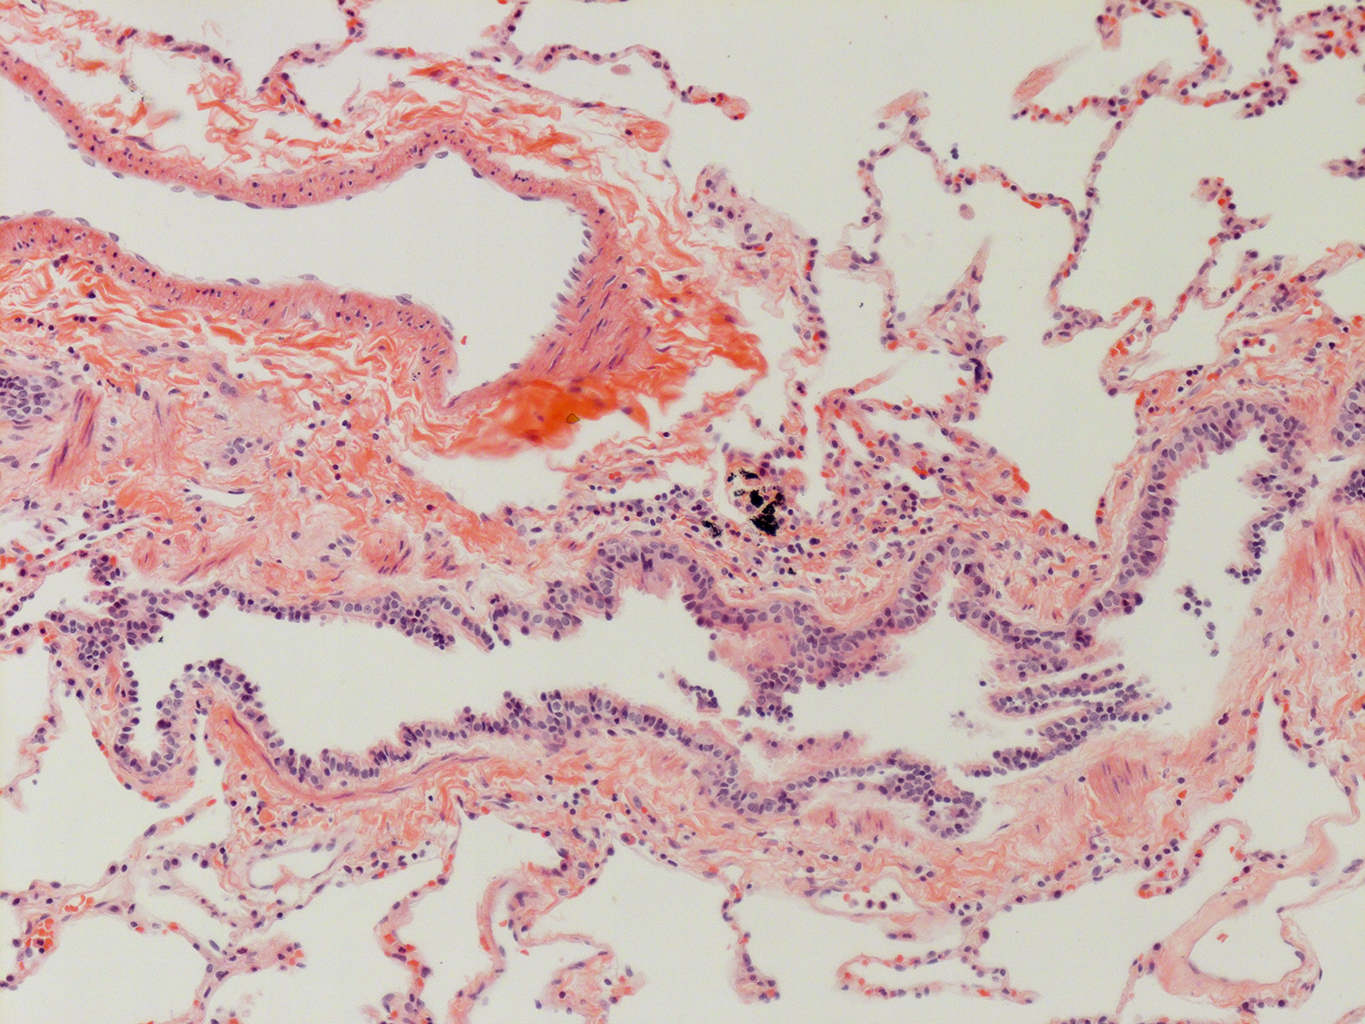

Donor tissue kindly provided by Dr. Scott Randell, University of North Carolina

Tissue Used:

LMHA-15-UNC-2017-12-19_D0037L.05HP_3_48

Gender: Male

Age:Â 43 Year Old

Race: Hispanic

Non-Smoker